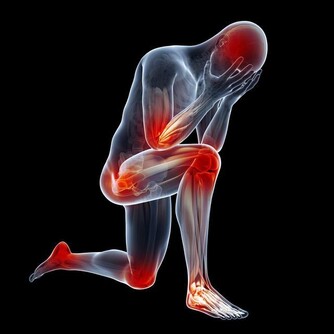

*****3.置換類的手術*****

有時需要換肝這種高難度的手術,手術過程複雜多樣,

在做這種手術時,對於病人來說需要開胸,自己衣服上可能攜帶一些病菌,在手術過程中造成不必要的影響,